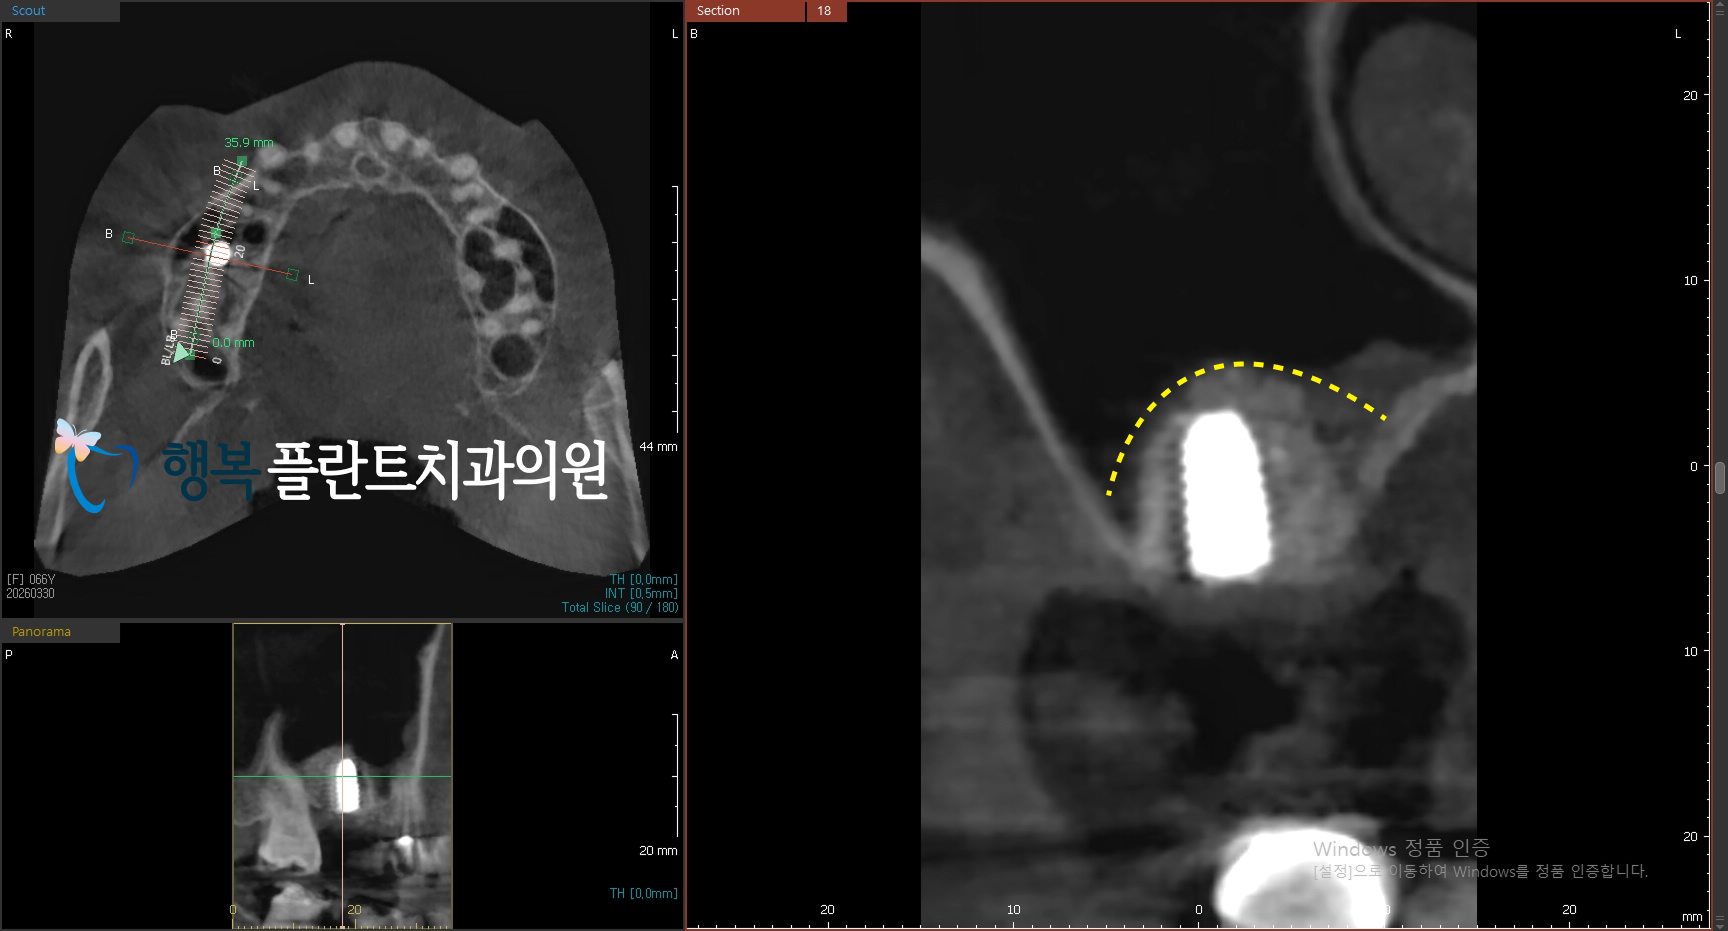

특히 이번 증례에서는 수압 거상을 활용한 상악동 거상술을 계획했습니다.

수압 거상은 일반적인 방식과 같이 기구로 억지로 밀어 올리는 방식이 아니라,

말 그대로 물의 압력을 이용해 상악동 막을 부드럽게 들어 올리는 방법입니다.

사실 상악동 막은 매우 얇고 예민하기 때문에

(흔히 계란의 속껍질 비슷하다고 표현합니다)

이런 방식은 막에 가해지는 직접적인 부담을 줄이면서 보다 섬세하게 접근하는 데 도움이 됩니다.

위 엑스레이 사진처럼 발치 후 보존술로 기반을 만들고, 충분한 치유 기간을 거친 뒤

필요한 시점에 맞춰 수압 거상을 통해 상악동 거상술을 시행함으로써 보다 안정적으로 임플란트를 식립할 수 있었는데요.

이렇게 이식된 뼈는 수개월에 걸쳐 환자 본인의 뼈와 임플란트까지 단단하게 결합되며

음식물을 저작할 수 있는 힘을 가지게 되는데 이 기간이 보통 4~5개월 정도 소요됩니다.